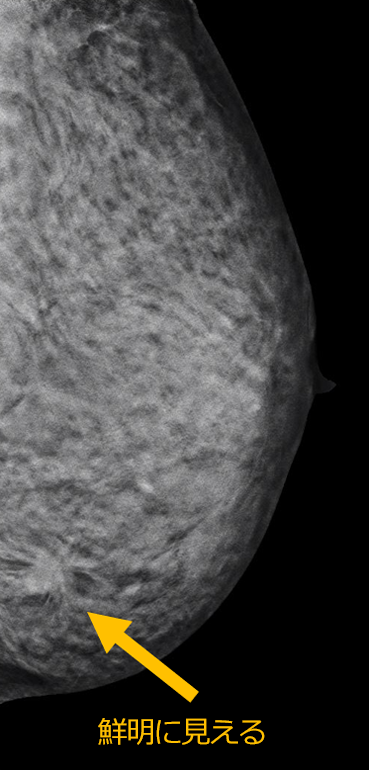

マンモグラフィ検査

マンモグラフィ検査

マンモグラフィ装置

マンモグラフィとは乳房のX線撮影のことです。乳癌の初期症状である小さな石灰化を写し出せるのが大きな特徴です。触診では触れない小さな乳がんを写し出すことが出来ます。

検査は上半身の衣類を脱いでから、専用の検査着に着替えて行います。乳腺組織を見やすくするために、乳房を圧迫板で片方ずつ挟んで撮影します。標準撮影は、左右の乳房を上下方向と斜め横方向の4回で検査時間は 10 分程度です。

圧迫伸展して撮影することで乳腺組織や病変の重なりが減り、正しい診断を行いやすくします。痛みをともなう場合もありますが、X線被曝量を減らす効果もあります。痛みが強いときは加減しますので、遠慮なくおっしゃってください。生理が終わってから1週間くらいの間は、乳腺が柔らかいので、痛みが減る傾向があります。

乳房トモシンセシスについて

トモシンセシス撮影とは、マンモグラフィの 3D 画像のことです。従来のマンモグラフィと同様に、乳房を挟んだ状態で複数の方向から撮影を行い、1mmスライスの細かい画像を作成します。通常のマンモグラフィに追加して撮影することで、乳腺の重なりによって発見しづらかった病変が見つけやすくなります。厚みのある乳房内の重なりを減らすことにより、乳腺の奥の病変の観察がしやすくなります。一回の圧迫時間は 10〜15 秒程度で、ぶれないように息を止めて撮影します。

2D撮影

トモシンセシス撮影